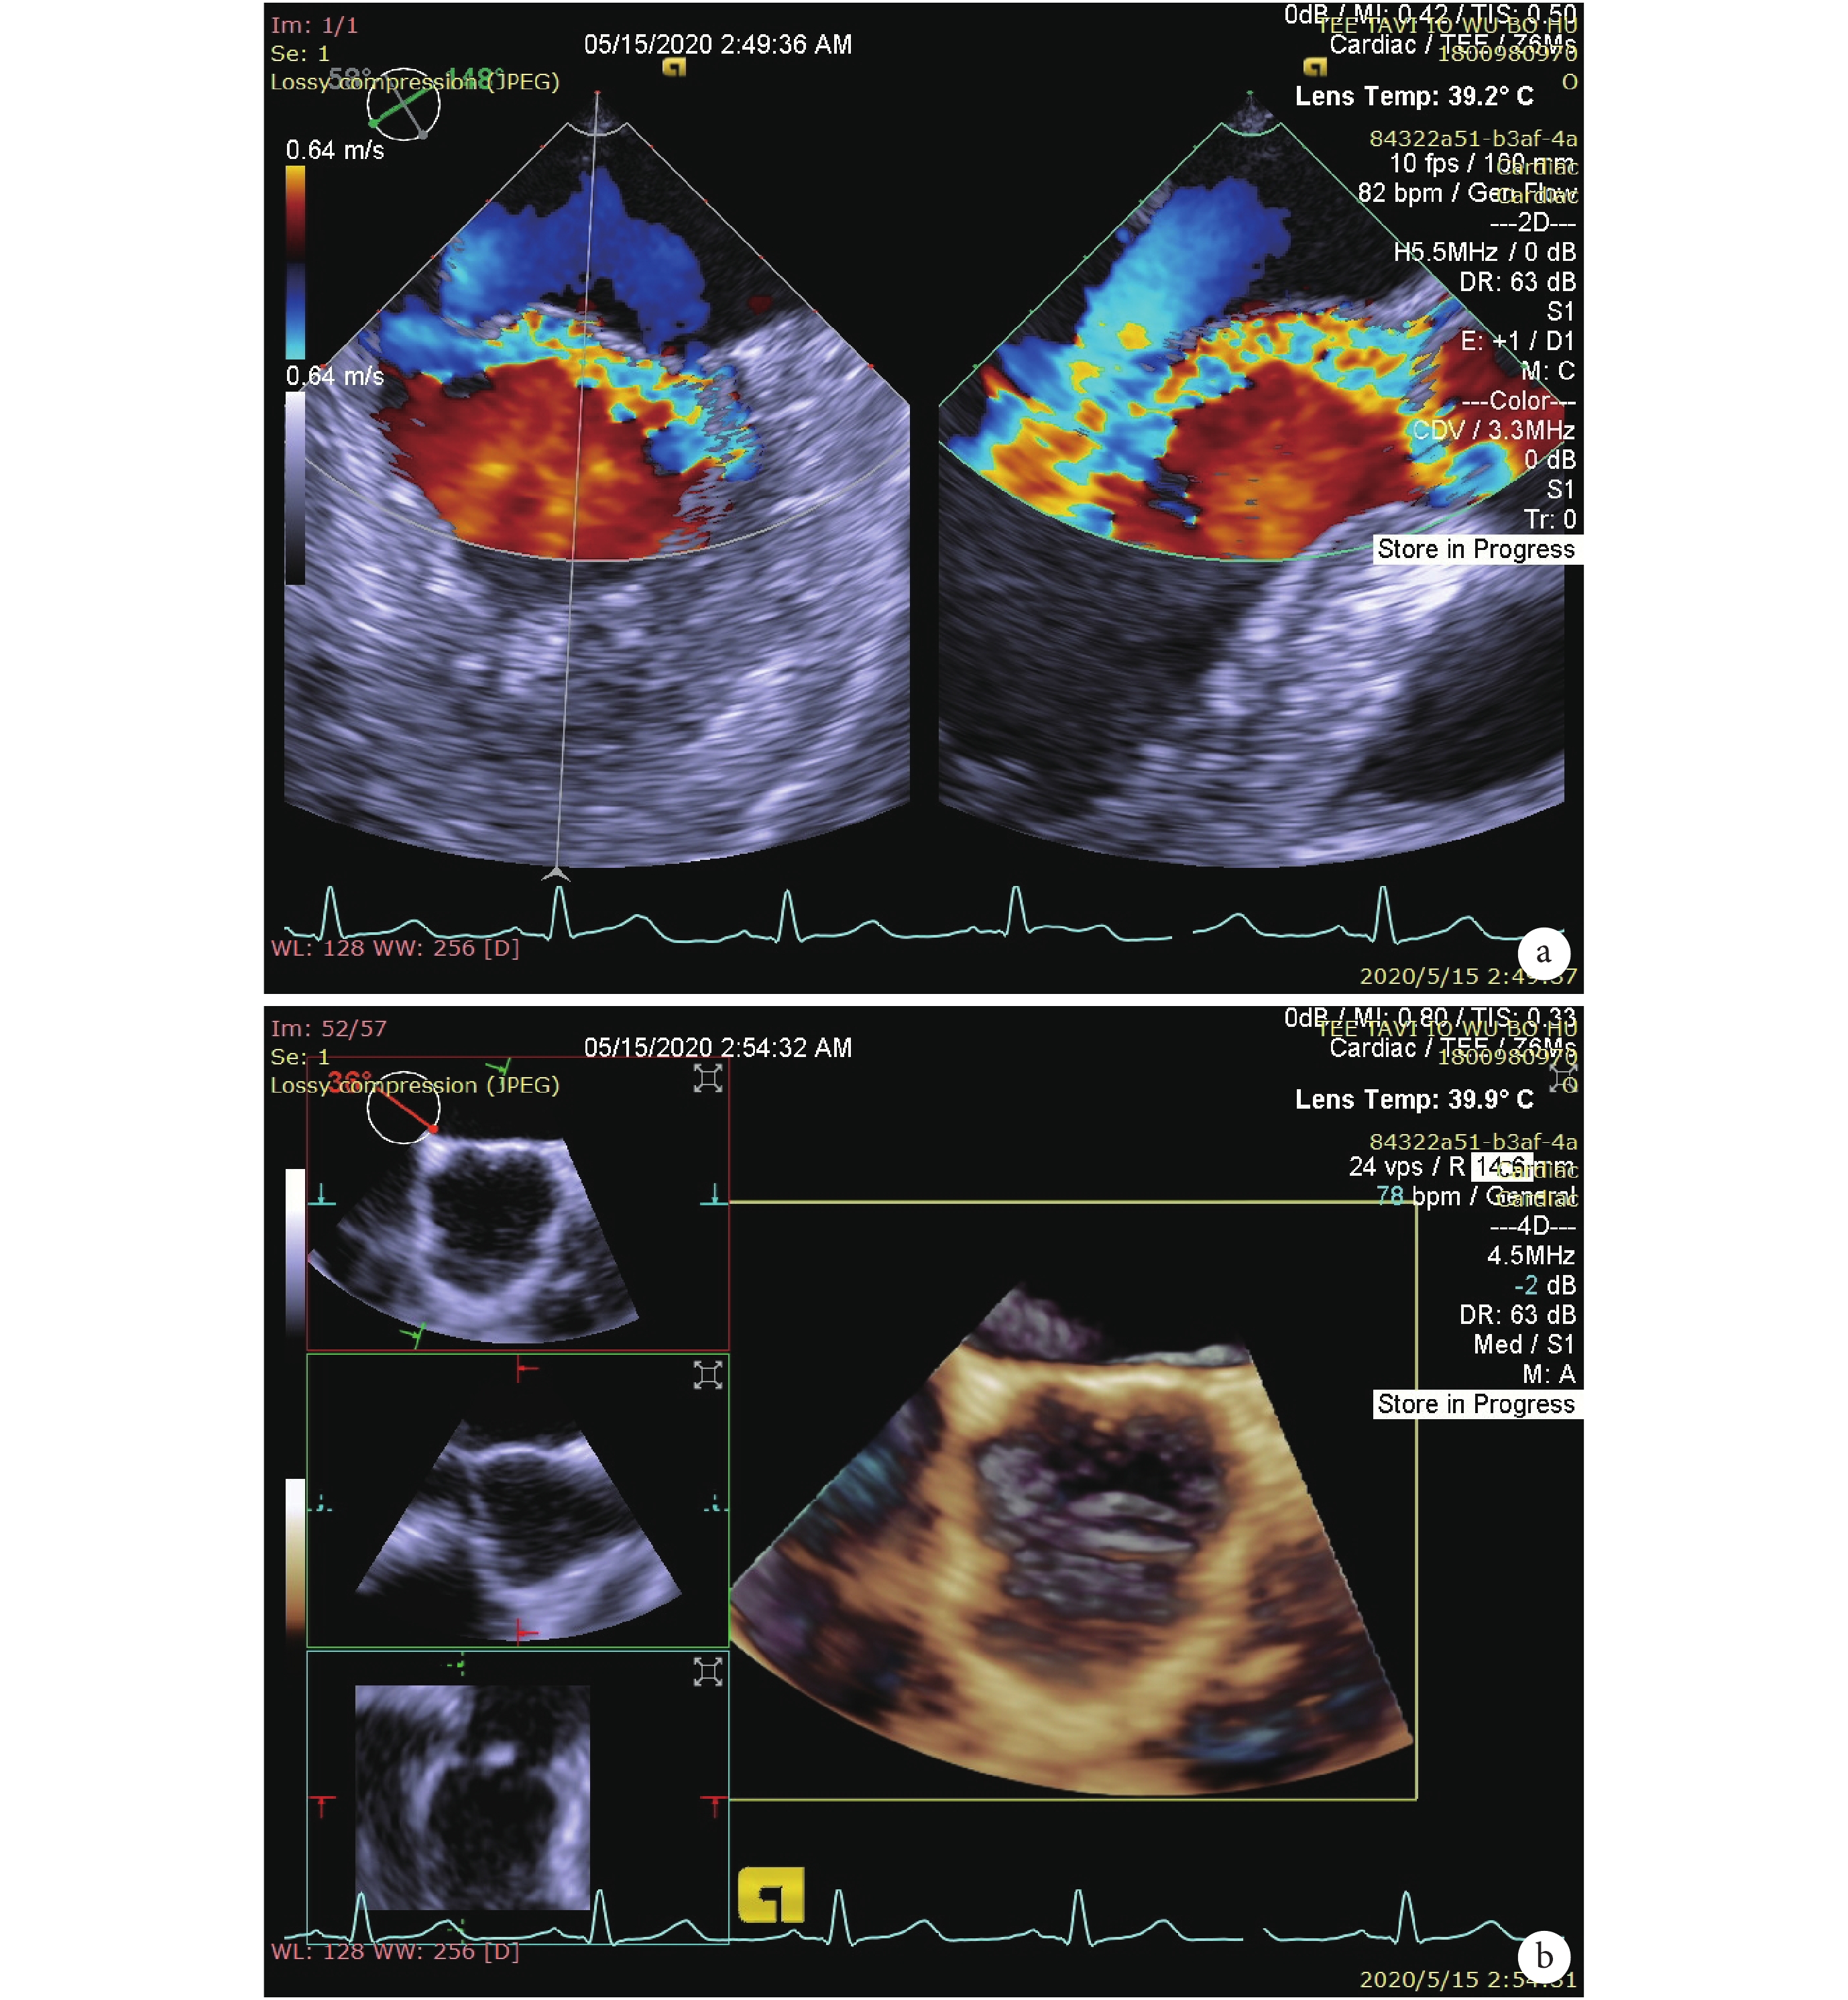

手術在介入雜交手術室進行,患者取仰臥位,常規全身麻醉后氣管插管,右側頸部植入頸內靜脈導管,必要時植入右側頸內靜脈心房起搏鞘管以便術中經頸靜脈植入 5 Fr 心房起搏導線,并調試是否正常工作。術前用經胸超聲心動圖先在左側胸部定位心尖搏動最強處,并在皮膚表面標記,后經口插入食管超聲探頭,再次評估患者心臟功能及主動脈瓣病變情況(圖 2)。

a:主動脈瓣大量反流,呈偏心性;b:主動脈右冠瓣發育較大,左冠瓣、無冠瓣發育較小